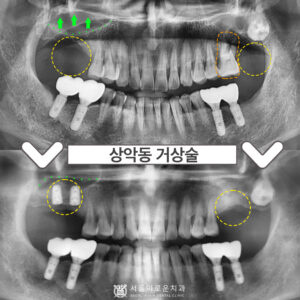

부천시청역치과 상악동 거상술을 동반해야 한다면 안녕하세요 😊 내 치아에 이로운 치과 서울이로운치과입니다 🙂 오늘은 임플란트 중에서도 난이도가 높은 “상악동 거상술” 케이스를 설명드리겠습니다. 왼쪽 위 어금니가 아파요. 이가 없는 부분도 있어서…